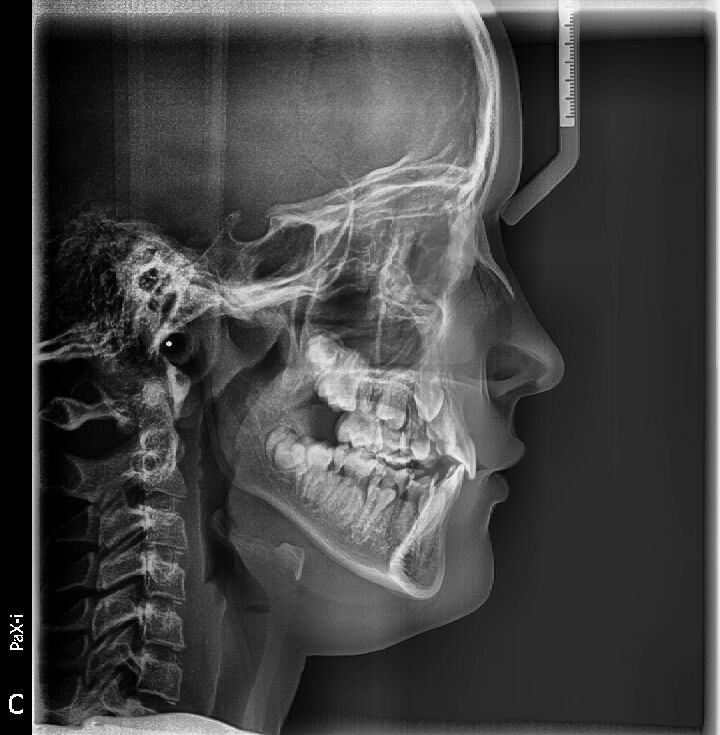

Zdjęcia panoramiczne i cefalometryczne.

Najnowocześniejszy cyfrowy aparat pantomograficzny Vatech Pax-i z przystawką cephalometryczną oraz techniką multifokalną , zapewnia najwyższą jakość zdjęć , potrzebnych do leczenia stomatologicznego i ortodontycznego.